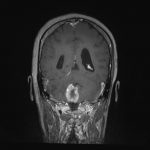

No.’25_108 手術前1

No.’25_108 手術前2